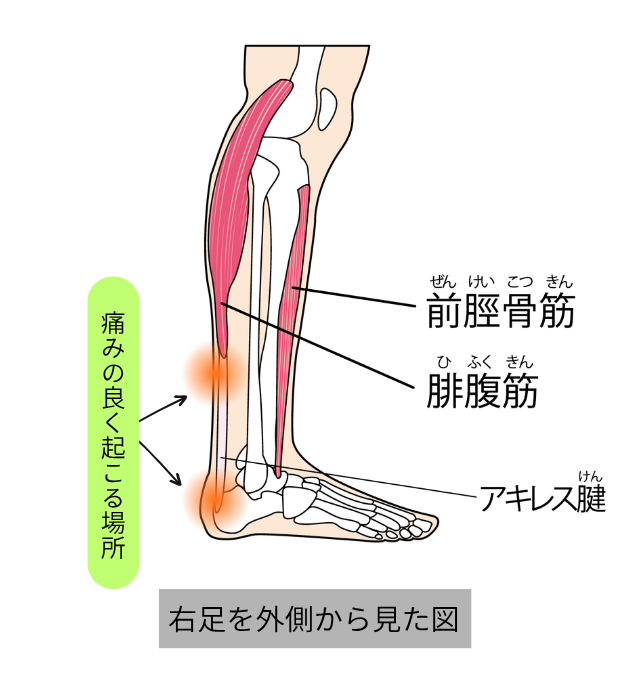

痛みが出やすい場所

アキレス腱の炎症は主に2つの部位に分けられます。

1.アキレス腱の中央部(腱の真ん中あたり)

・ふくらはぎと踵のちょうど間、腱の途中に炎症が起きるタイプ

・ランニングやジャンプの繰り返しで起こりやすい

・押すと硬くしこりのように感じることもある

2.アキレス腱付着部(かかとの骨に近い部分)

・踵の少し上、腱が骨にくっつく部分に炎症が出るタイプ

・シューズのかかとが当たって痛むことも多い

・骨の出っ張り(骨化や隆起)が伴う場合もある